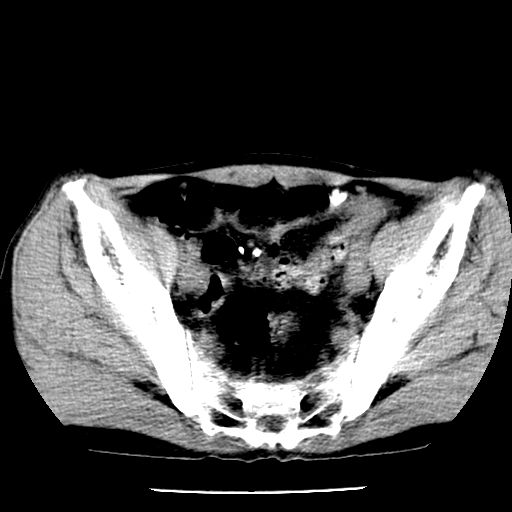

两肺结核并右侧胸腔积液;脾脏、腹腔及腹膜后淋巴结结核[陈旧性];肝内胆管结石

胸部腹部都是结核(双肺。纵隔淋巴结,肝脏,脾脏,肠系膜)

两肺结核并右侧胸腔积液;脾脏、腹腔及腹膜后淋巴结结核[陈旧性];肝内胆管结石。直肠息肉?

一元论——结核。